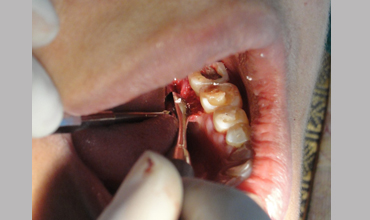

NON SURGICAL MANAGEMENT OF ENDODONTIC LESION AND SURGICAL MANAGEMENT OF PERIODONTIC LESION